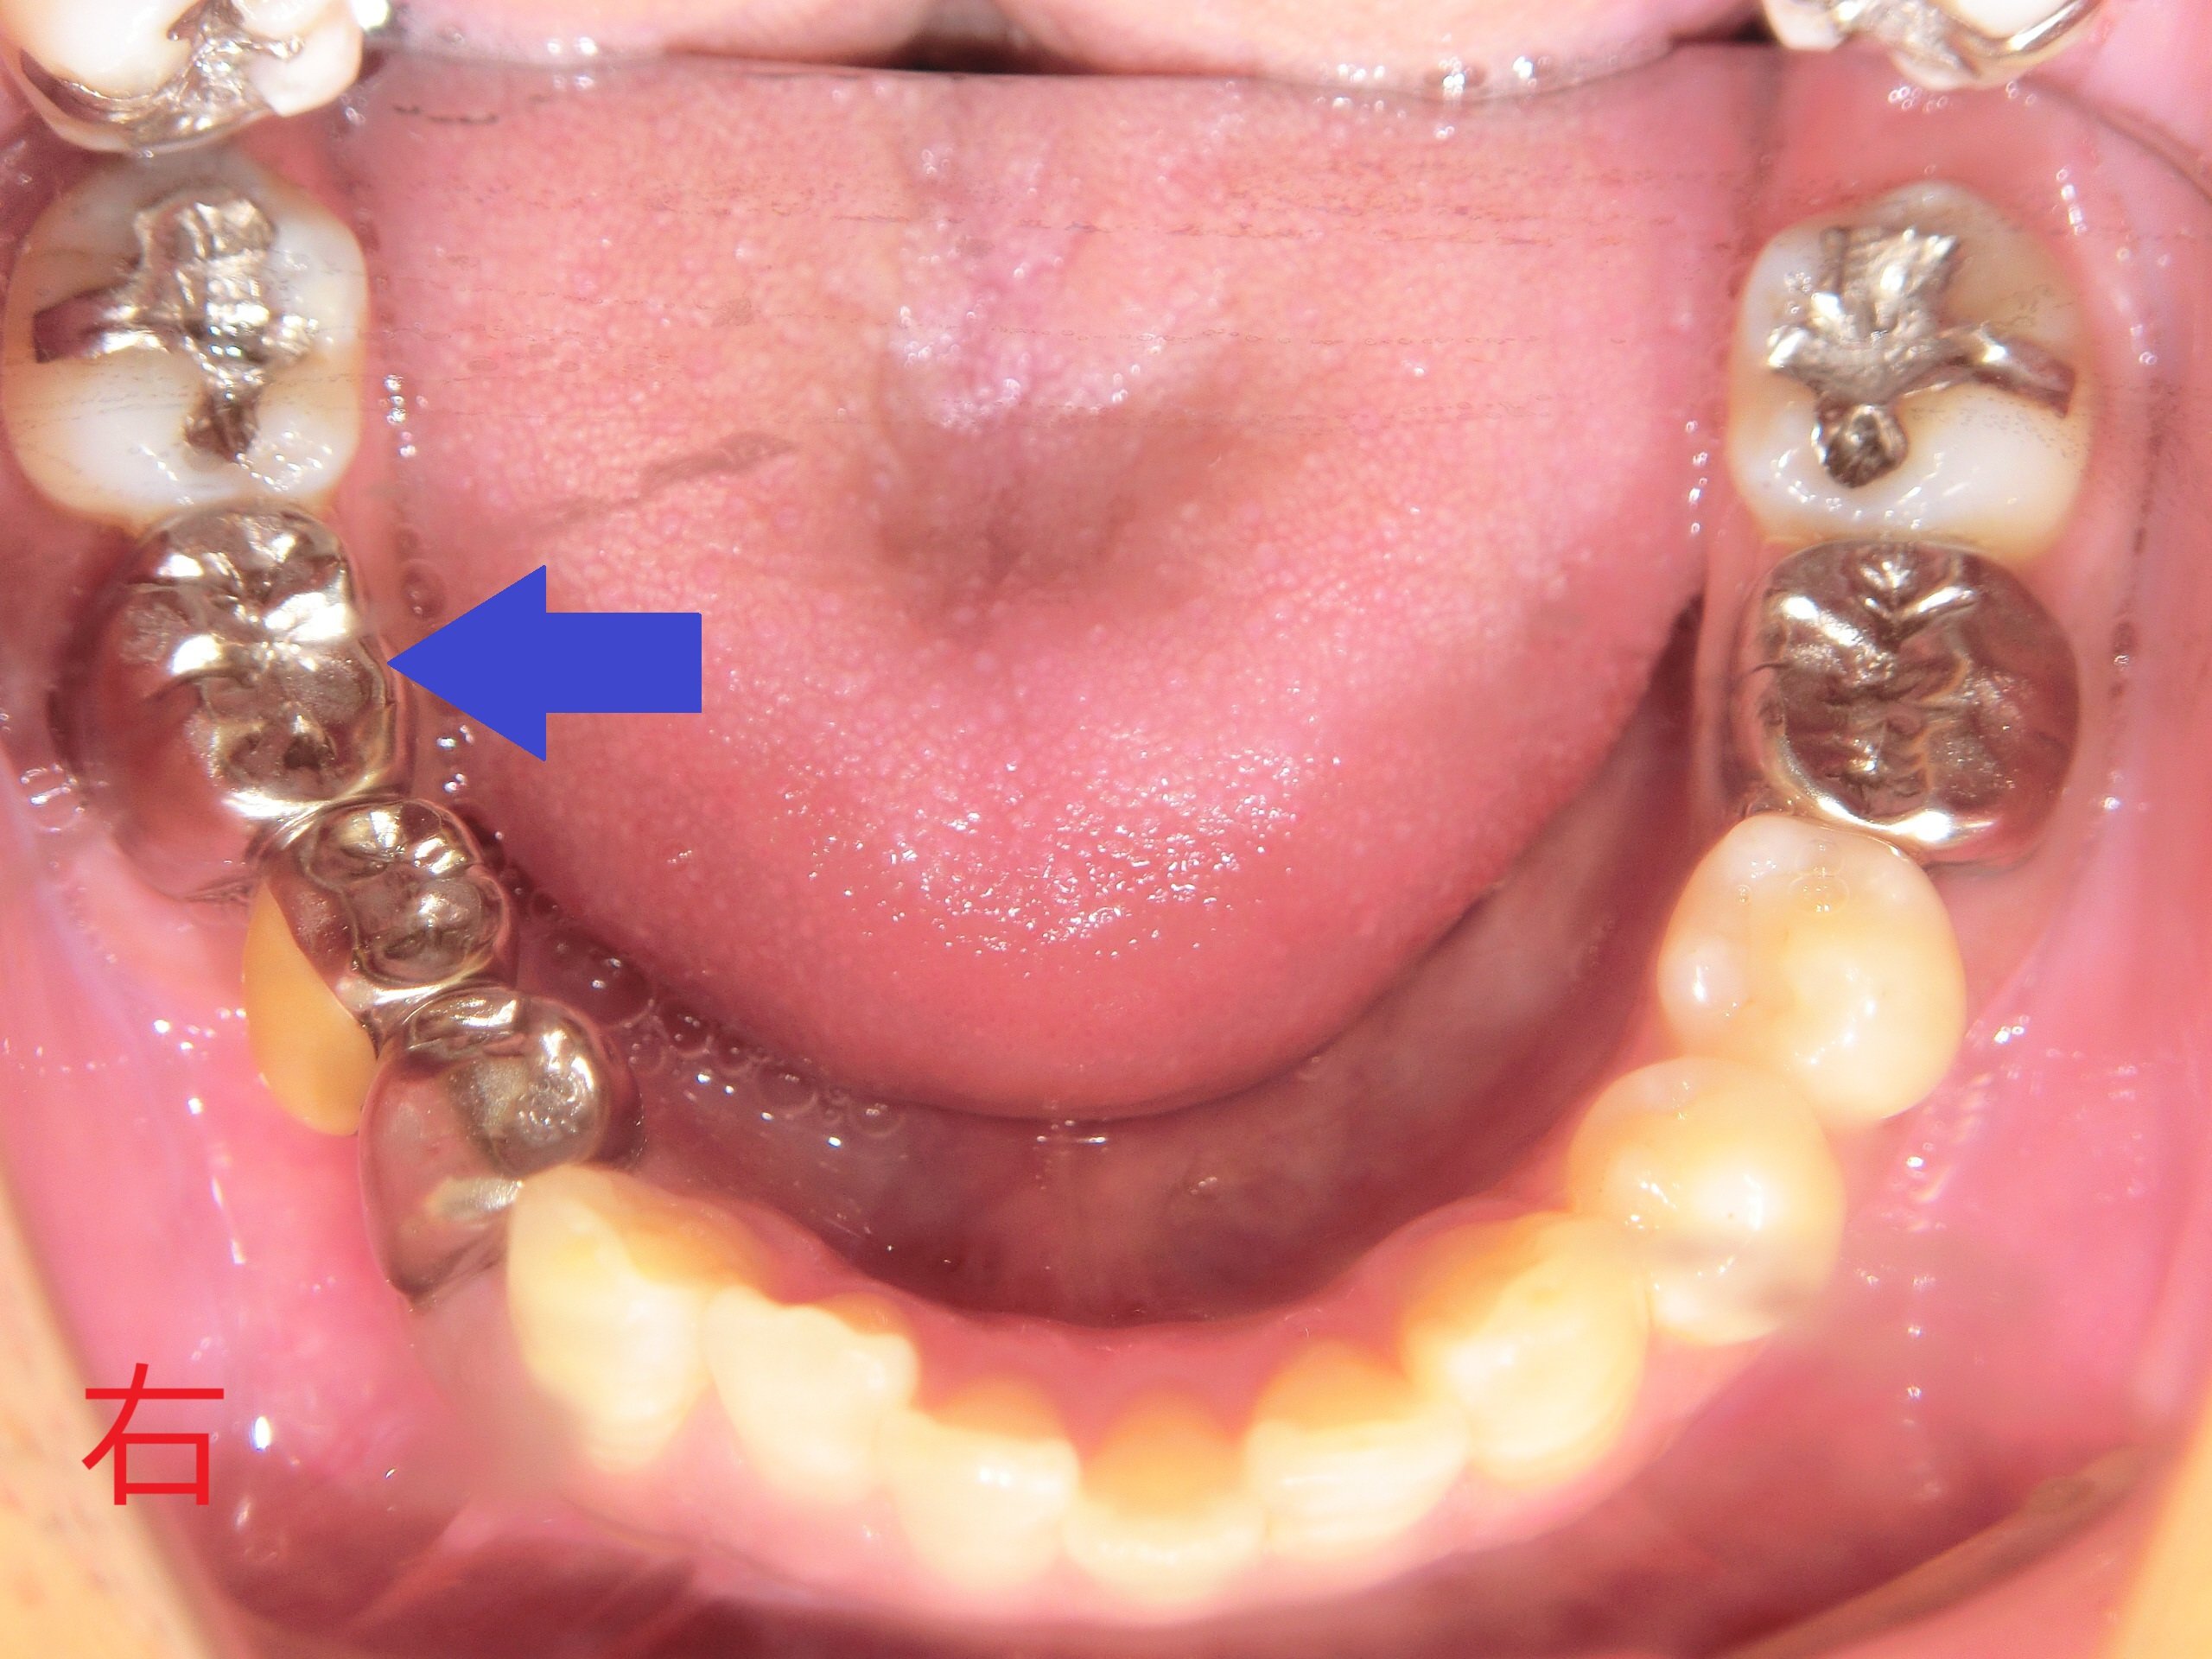

この患者様は、青色矢印の位置にブリッジ(両隣の歯を銀歯に加工し、中央の歯の欠損部分を補う固定式の補綴装置)を装着されていましたが、後方の銀歯周囲に歯茎の腫れがみられたため、当院を受診されました。

診断の結果、後方の銀歯を支える歯の根が完全に破折しており、抜歯が必要な状態でした。

青色矢印の歯が破折し、歯根の周囲の骨が吸収されている様子が確認されます。

神経を除去した歯は、神経が残っている歯と比較して強度が著しく低下するため、歯根破折のリスクが高くなります。実際、矢印の前方にある歯も神経を除去しており、同様のリスクが懸念されます。